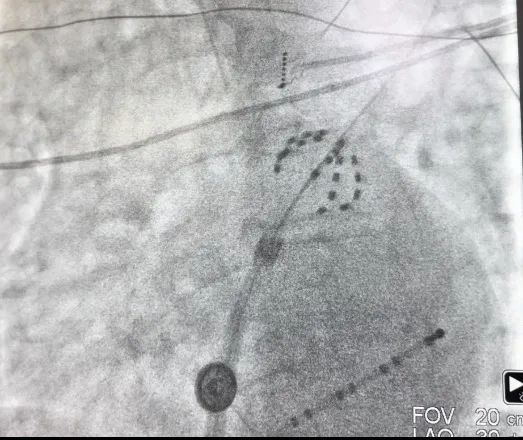

上图为X线下farapulse导管的两种形态:网篮状(左)和花瓣

脉冲消融术后,经验证患者的肺静脉均完成了电隔离。其中第一位患者脉冲消融时长为13分钟;第二位患者脉冲消融时长为25分钟,左心耳封堵时长20分钟,两台手术均高效完成,术后两名患者各项体征正常,安全返回病房,无任何并发症或不良事件。